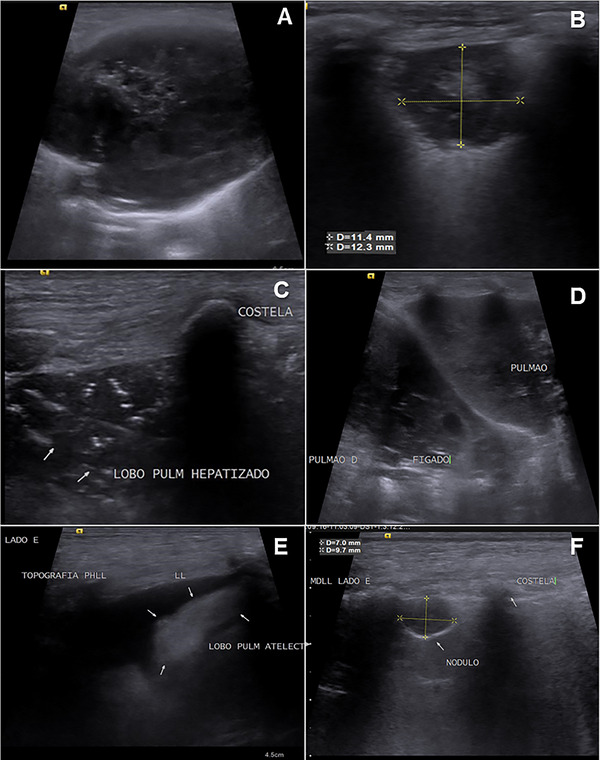

本研究旨在评估声辐射力脉冲(ARFI)弹性成像作为狗肺部病变诊断工具的应用。该研究包括在2020年至2022年期间被兽医教学医院放射科检查肺部病变的狗。肺病变的特征评估使用x线摄影作为定位的筛选工具,b超用于组织表征,随后进行定性(弹性图等级1-3)和定量(剪切波速- swv)弹性图评估。根据临床、超声、影像学、组织病理学和/或细胞学检查结果,将病变分为以下几类:实变、肺不张或肿瘤(结节和肿块)。26只狗符合资格标准,被纳入研究。在某些情况下,同一只狗有不止一种类型的病变,导致35个肺病变的评估:13个肿块,8个结节,8个实变,4个肺不张区。定量弹性成像评估显示,与实变(2.94±0.64 m/s)、结节(2.85±1.40 m/s)和肿块(3.13±1.45 m/s)相比,肺不张病变的刚度(1.48±0.35 m/s)较低,但由于良性病变数量有限,没有明确的诊断临界值。结果表明,ARFI弹性成像可以作为一种有价值的补充工具,与临床数据和传统成像技术一起评估狗的肺部病变。未来的研究需要更大样本量的良性肺实质病变,以进一步探索弹性成像预测恶性肿瘤的潜力。

This study aimed to evaluate the use of acoustic radiation force impulse (ARFI) elastography as a diagnostic tool for lung lesions in dogs. Dogs referred to the Radiology Department of the Veterinary Teaching Hospital between 2020 and 2022 for the detection of lung lesions were included in the study. The characteristics of the lung lesions were assessed using radiography as a screening tool for localization, B-mode ultrasound for tissue characterization, and subsequently, both qualitative (elastogram grades 1-3) and quantitative (shear wave velocity-SWV) elastographic evaluations. The lesions were classified based on clinical, ultrasound, radiographic, histopathological, and/or cytological findings into the following categories: consolidations, atelectasis, or neoplasms (nodules and masses). Twenty-six dogs met the eligibility criteria and were included in the study. In some cases, the same dog had more than one type of lesion, resulting in the evaluation of 35 lung lesions: 13 masses, 8 nodules, 8 consolidations, and 4 areas of atelectasis. The quantitative elastographic evaluation revealed lower stiffness in atelectatic lesions (1.48 ± 0.35 m/s) compared with consolidations (2.94 ± 0.64 m/s), nodules (2.85 ± 1.40 m/s), and masses (3.13 ± 1.45 m/s), although no definitive diagnostic cut-off value was established, due to the limited number of benign lesions. The results suggest that ARFI elastography can be a valuable complementary tool alongside clinical data and conventional imaging techniques in assessing lung lesions in dogs. Future studies with a larger sample size of benign parenchymal lung lesions are needed to further explore the potential of elastography for predicting malignancy.